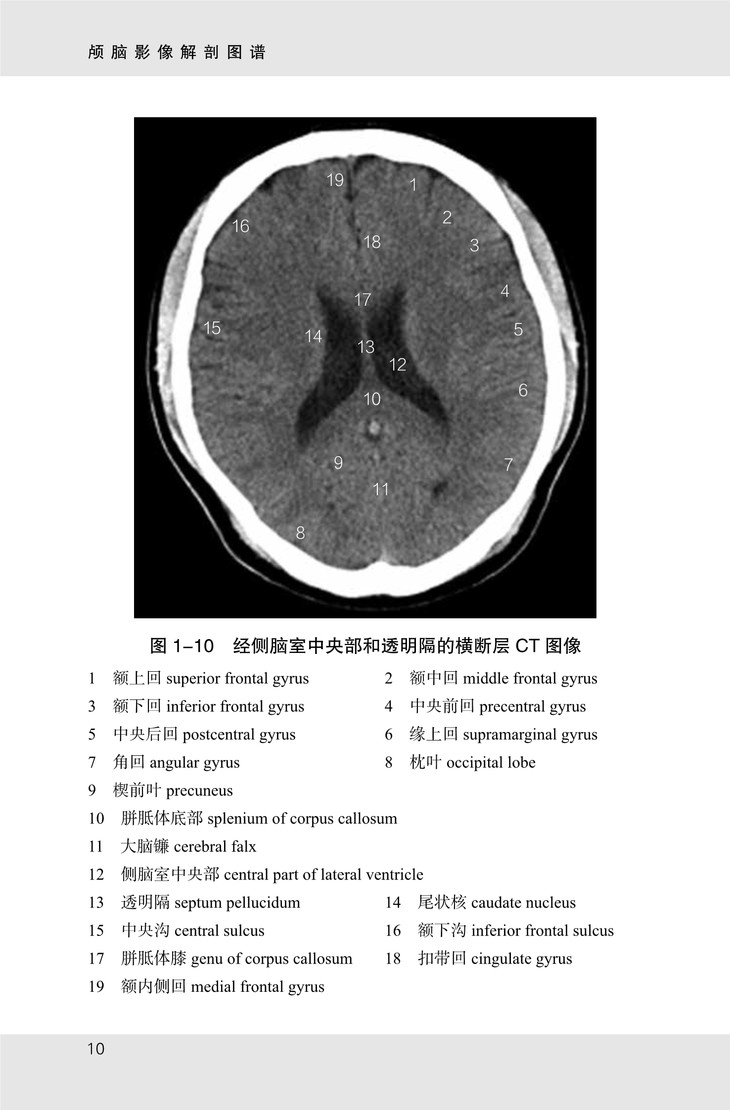

《颅脑影像解剖图谱》共有图像 175 幅,包括以下四个部分:

(1)颅脑 CT 图像,从颅顶至枕骨大孔共有横断层图像 21 幅,扫描基线为眦耳线;